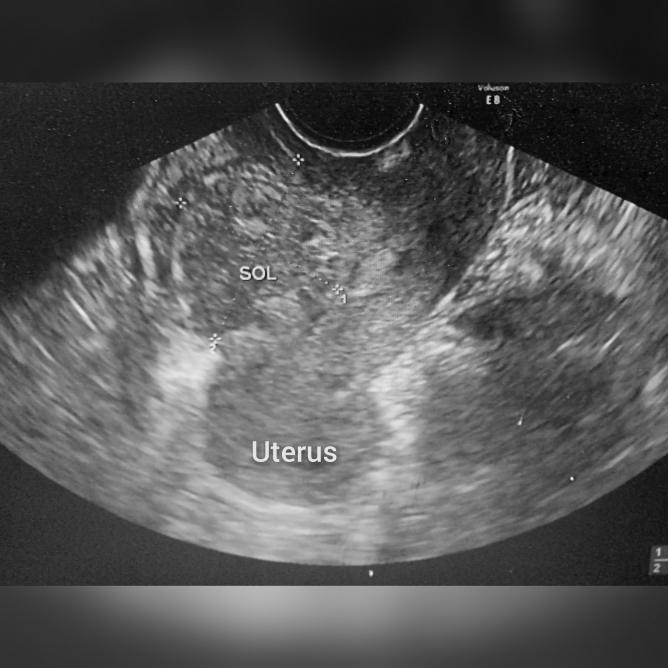

Disruption of Cesarean Scar with Uterovesical Space Hematocele Mimicking an Endometrioma.

Our case highlights an extreme form of cesarean scar defect with diagnostic and surgical challenges. The unusual presentation of a large extrauterine-encapsulated collection of altered blood and hemosiderin behind the posterior bladder wall that communicated with the endometrial cavity, through a full thickness myometrial discontinuity, at the site of a previous cesarean section, mimicked an endometrioma in an unusual location. This case report not only highlights the diagnostic challenge involved in this case but also highlights the surgical steps involved in the laparoscopic management of this extreme end of the spectrum of cesarean scar defects. We have attached a video of the laparoscopic surgery with step-wise description to shed more light on the management of this rare complication.

我们的病例突出了一种剖宫产瘢痕缺损的极端形式,存在诊断和手术挑战。膀胱后壁后方出现大量宫外包裹性陈旧血液和含铁血黄素聚集,通过既往剖宫产部位的全层子宫肌层连续性中断与子宫内膜腔相通,这种不寻常的表现酷似罕见部位的子宫内膜瘤。本病例报告不仅突出了该病例所涉及的诊断挑战,还突出了剖宫产瘢痕缺损这一谱系极端情况的腹腔镜管理所涉及的手术步骤。我们附上了腹腔镜手术视频及逐步描述,以更清楚地说明这种罕见并发症的处理。